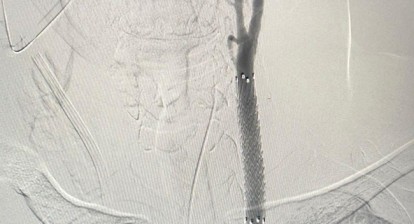

6.3. Mechanical Circulatory Support (MCS)

The Intra-Aortic Balloon Pump (IABP), a temporary MCS device, enhances the myocardial oxygen supply-demand ratio by lowering impedance to systolic ejection and improving coronary perfusion. The utility of the IABP expanded dramatically when invasive cardiologists adopted the technique of percutaneous insertion, eliminating the need for surgical cut-down.

For long-term support, the development of Ventricular Assist Devices (VADs) has been driven largely by the persistent shortage of donor organs for heart transplantation. VADs, and in some cases temporary total artificial hearts, serve as a bridge to transplantation or as destination therapy for patients ineligible for transplants. Modern devices are predominantly continuous-flow (non-pulsatile) systems, representing a significant technological advance over earlier pulsatile devices.

Advanced organ support represents highly aggressive and resource-intensive interventions. While these technologies are often life-saving, they introduce new risks. For instance, ECMO is associated with higher rates of major bleeding , and MCS therapy still faces challenges related to adverse events, requiring continuous strategies to improve biocompatibility. The rapid technological expansion, such as the less-invasive insertion of devices like the IABP, requires rigorous patient selection and continuous refinement of clinical protocols to ensure that the principle of beneficence (the potential for survival) is continuously balanced against the complexity and potential for nonmaleficence (device-related complications).